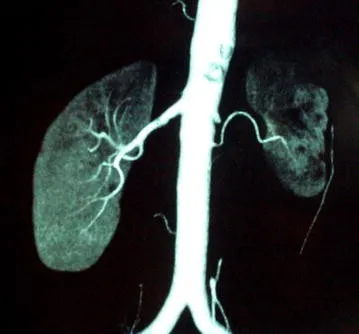

Amiloidose renal: aspectos sobre patogenia, diagnóstico e proteomica

Este vídeo apresenta, de forma didática e baseada em evidências, os principais achados da tese de doutorado sobre amiloidose renal, com foco em proteômica glomerular e ativação do complemento. São discutidos aspectos diagnósticos, implicações fisiopatológicas e correlações clínico-patológicas relevantes para a prática do nefrologista. O conteúdo sintetiza dados inéditos de matriz extracelular glomerular e diferencia perfis entre subtipos de amiloidose. Trata-se de um material aprofundado e acessível, ideal para atualização de especialistas na área.